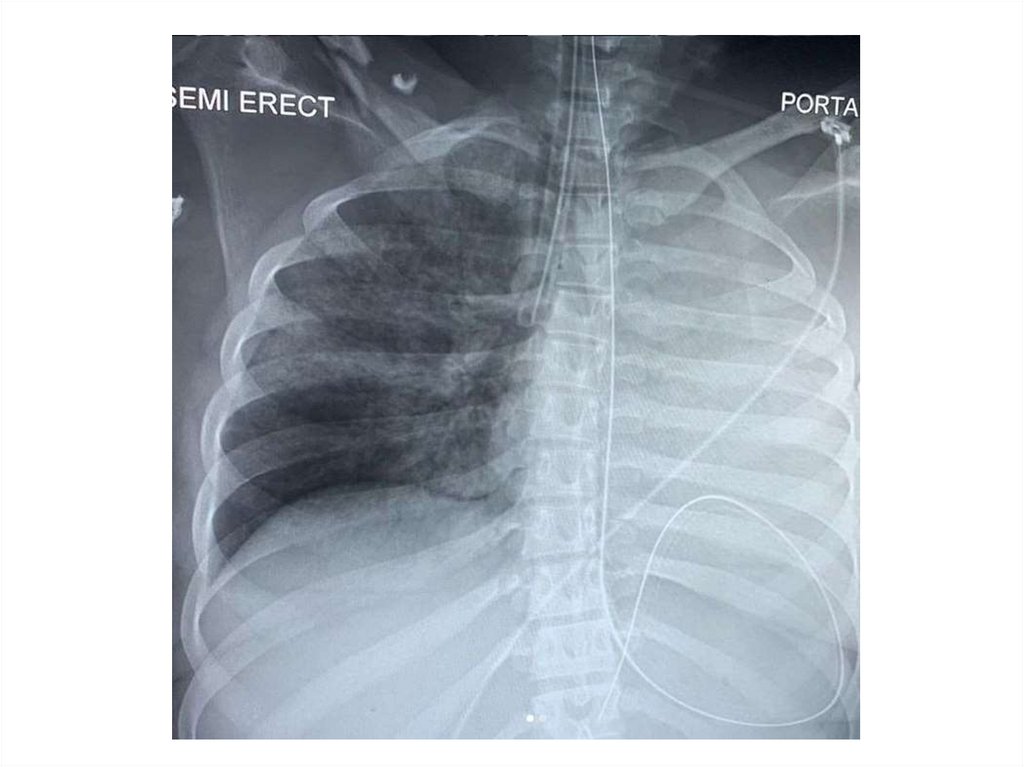

Назовите

• Вид исследования

• Область исследования

• Патологию